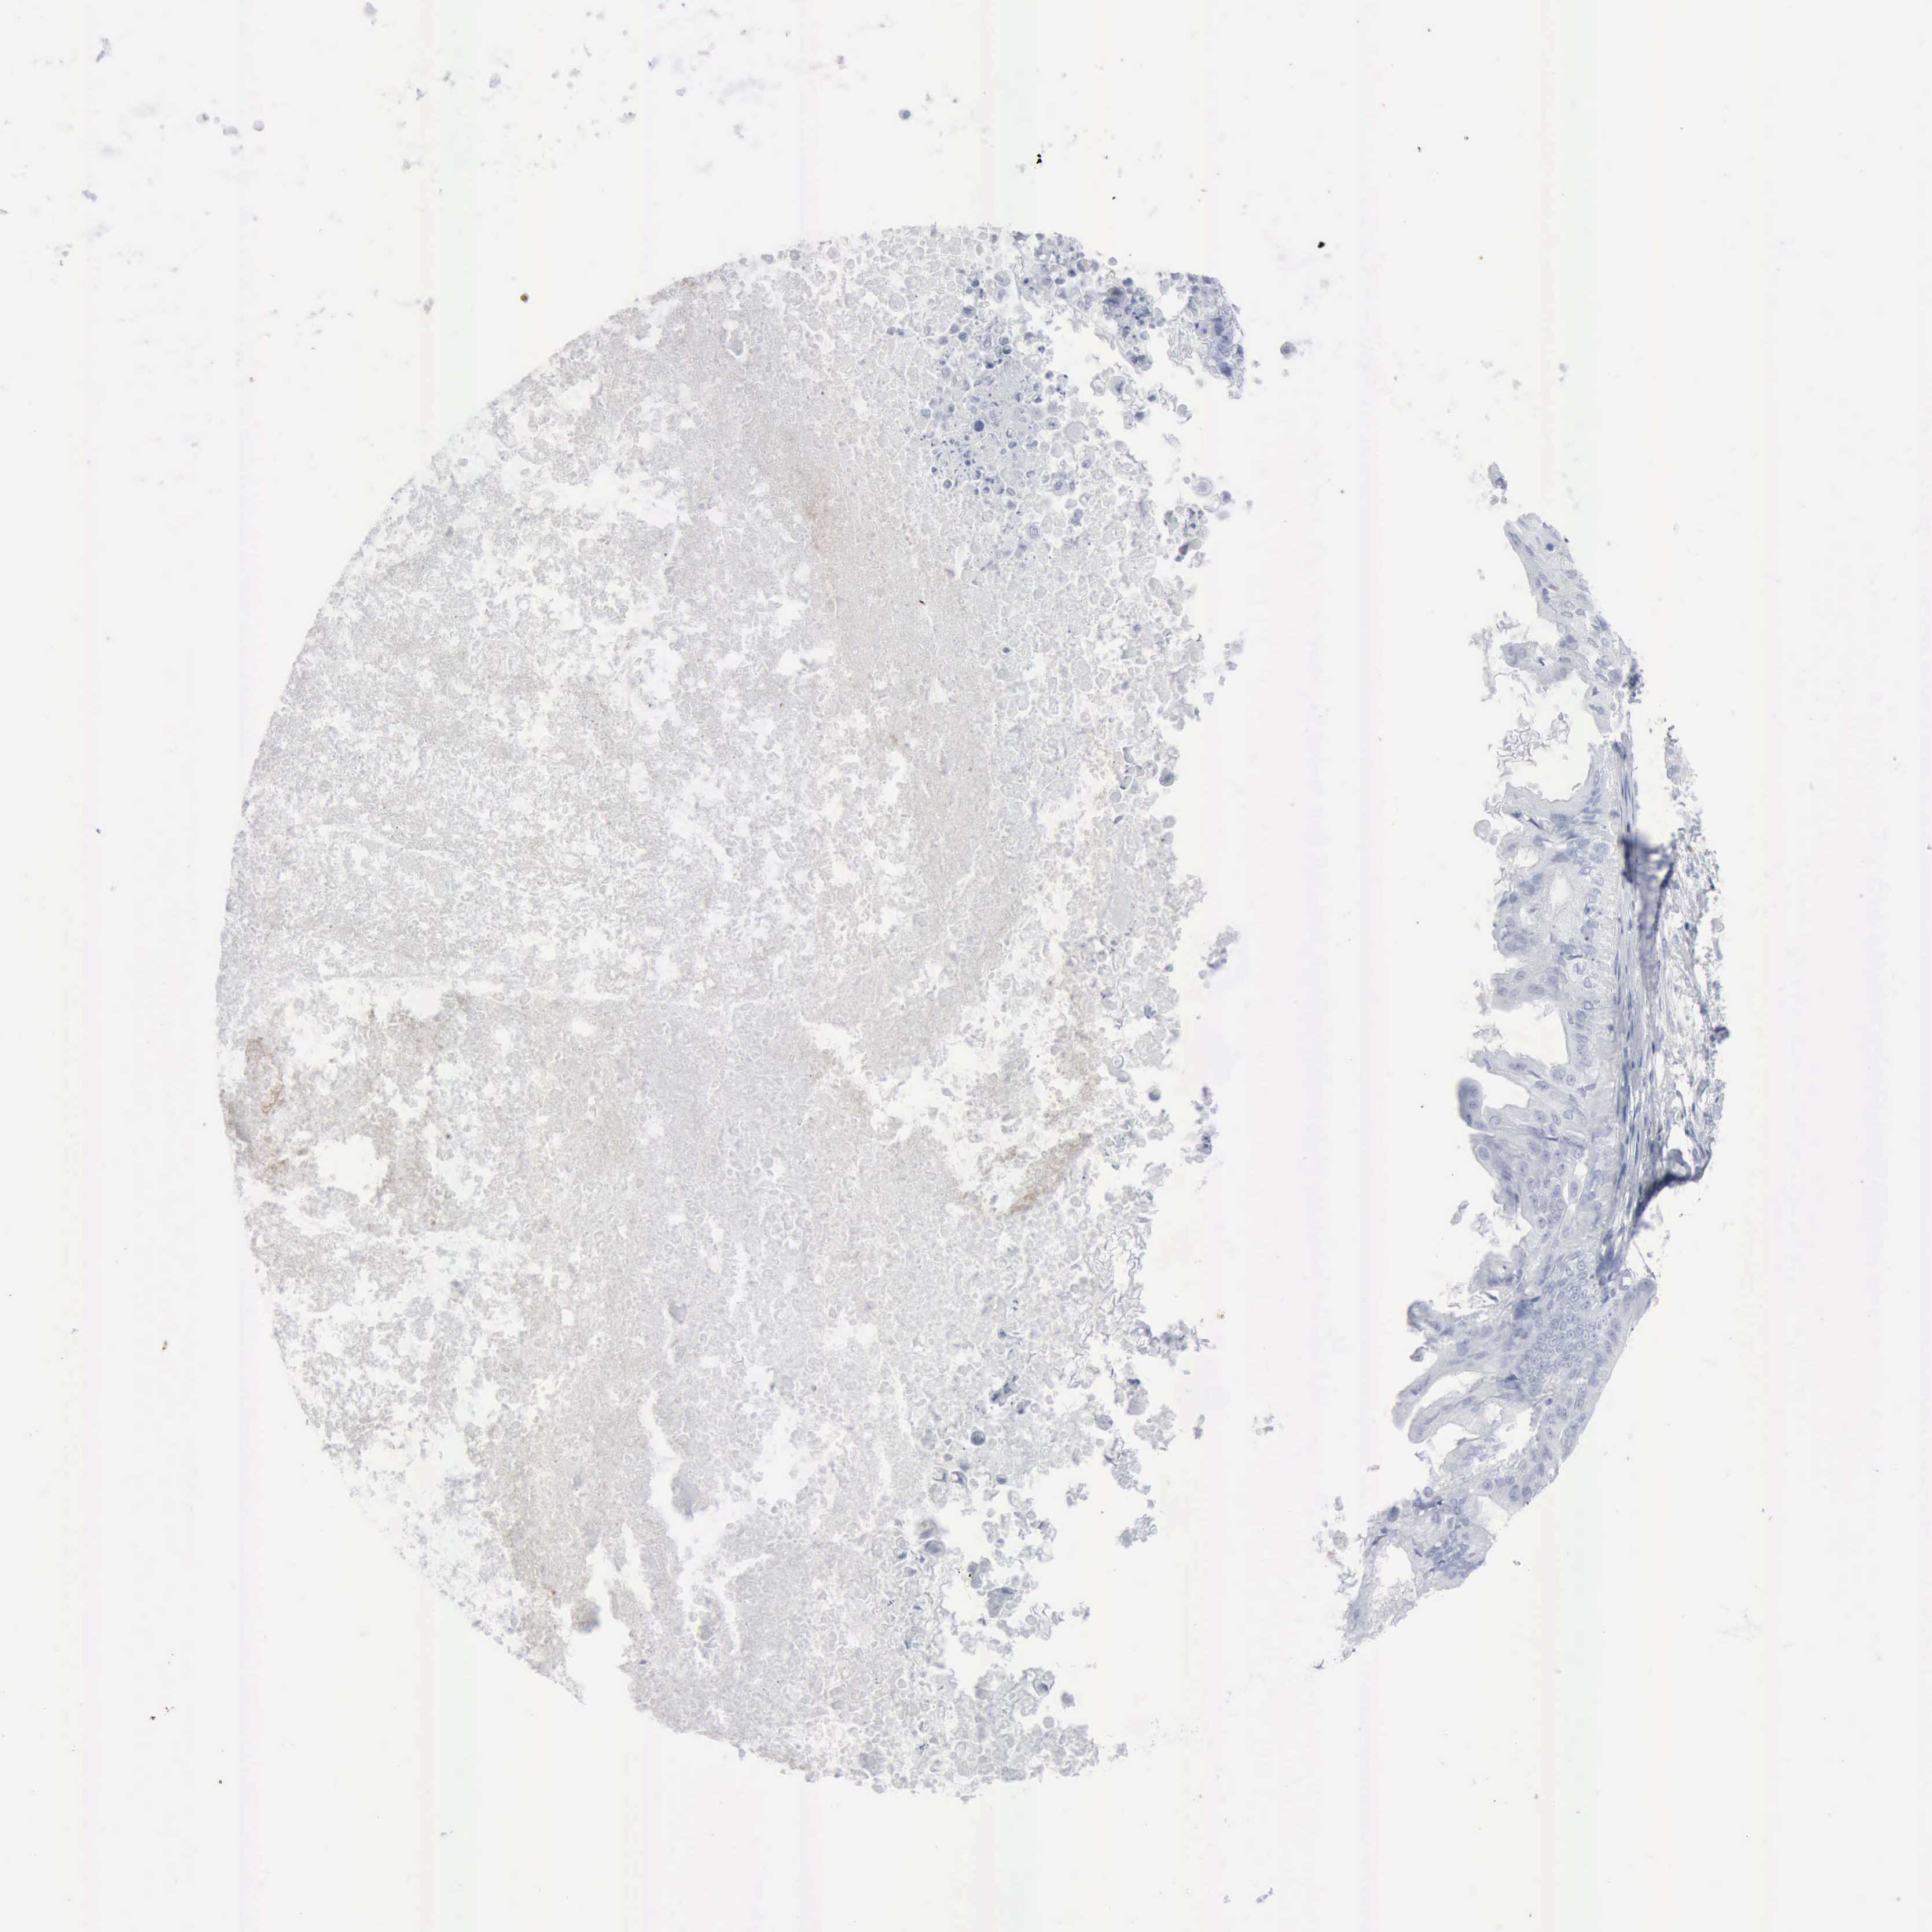

OVARIAN CANCER - Protein expressioni

A mouse-over function shows sample information and annotation data. Click on an image to view it in a full screen mode. Samples can be filtered based on level of antibody staining by selecting one or several of the following categories: high, medium, low and not detected. The assay and annotation is described here.

Note that samples used for immunohistochemistry by the Human Protein Atlas do not correspond to samples in the TCGA dataset.

Antibody stainingi

Antibody staining in the annotated cell types in the current human tissue is reported as not detected, low, medium, or high, based on conventional immunohistochemistry profiling in selected tissues. This score is based on the combination of the staining intensity and fraction of stained cells.

Each image is clickable and will lead to virtual microscopy that enables deeper exploration of all samples and also displays staining intensity scores, fraction scores and subcellular localization as well as patient and tissue information for each sample.

Antibody HPA000237

Antibody HPA000966

Cystadenocarcinoma, mucinous, NOS

Carcinoma, endometroid

Cystadenocarcinoma, serous, NOS